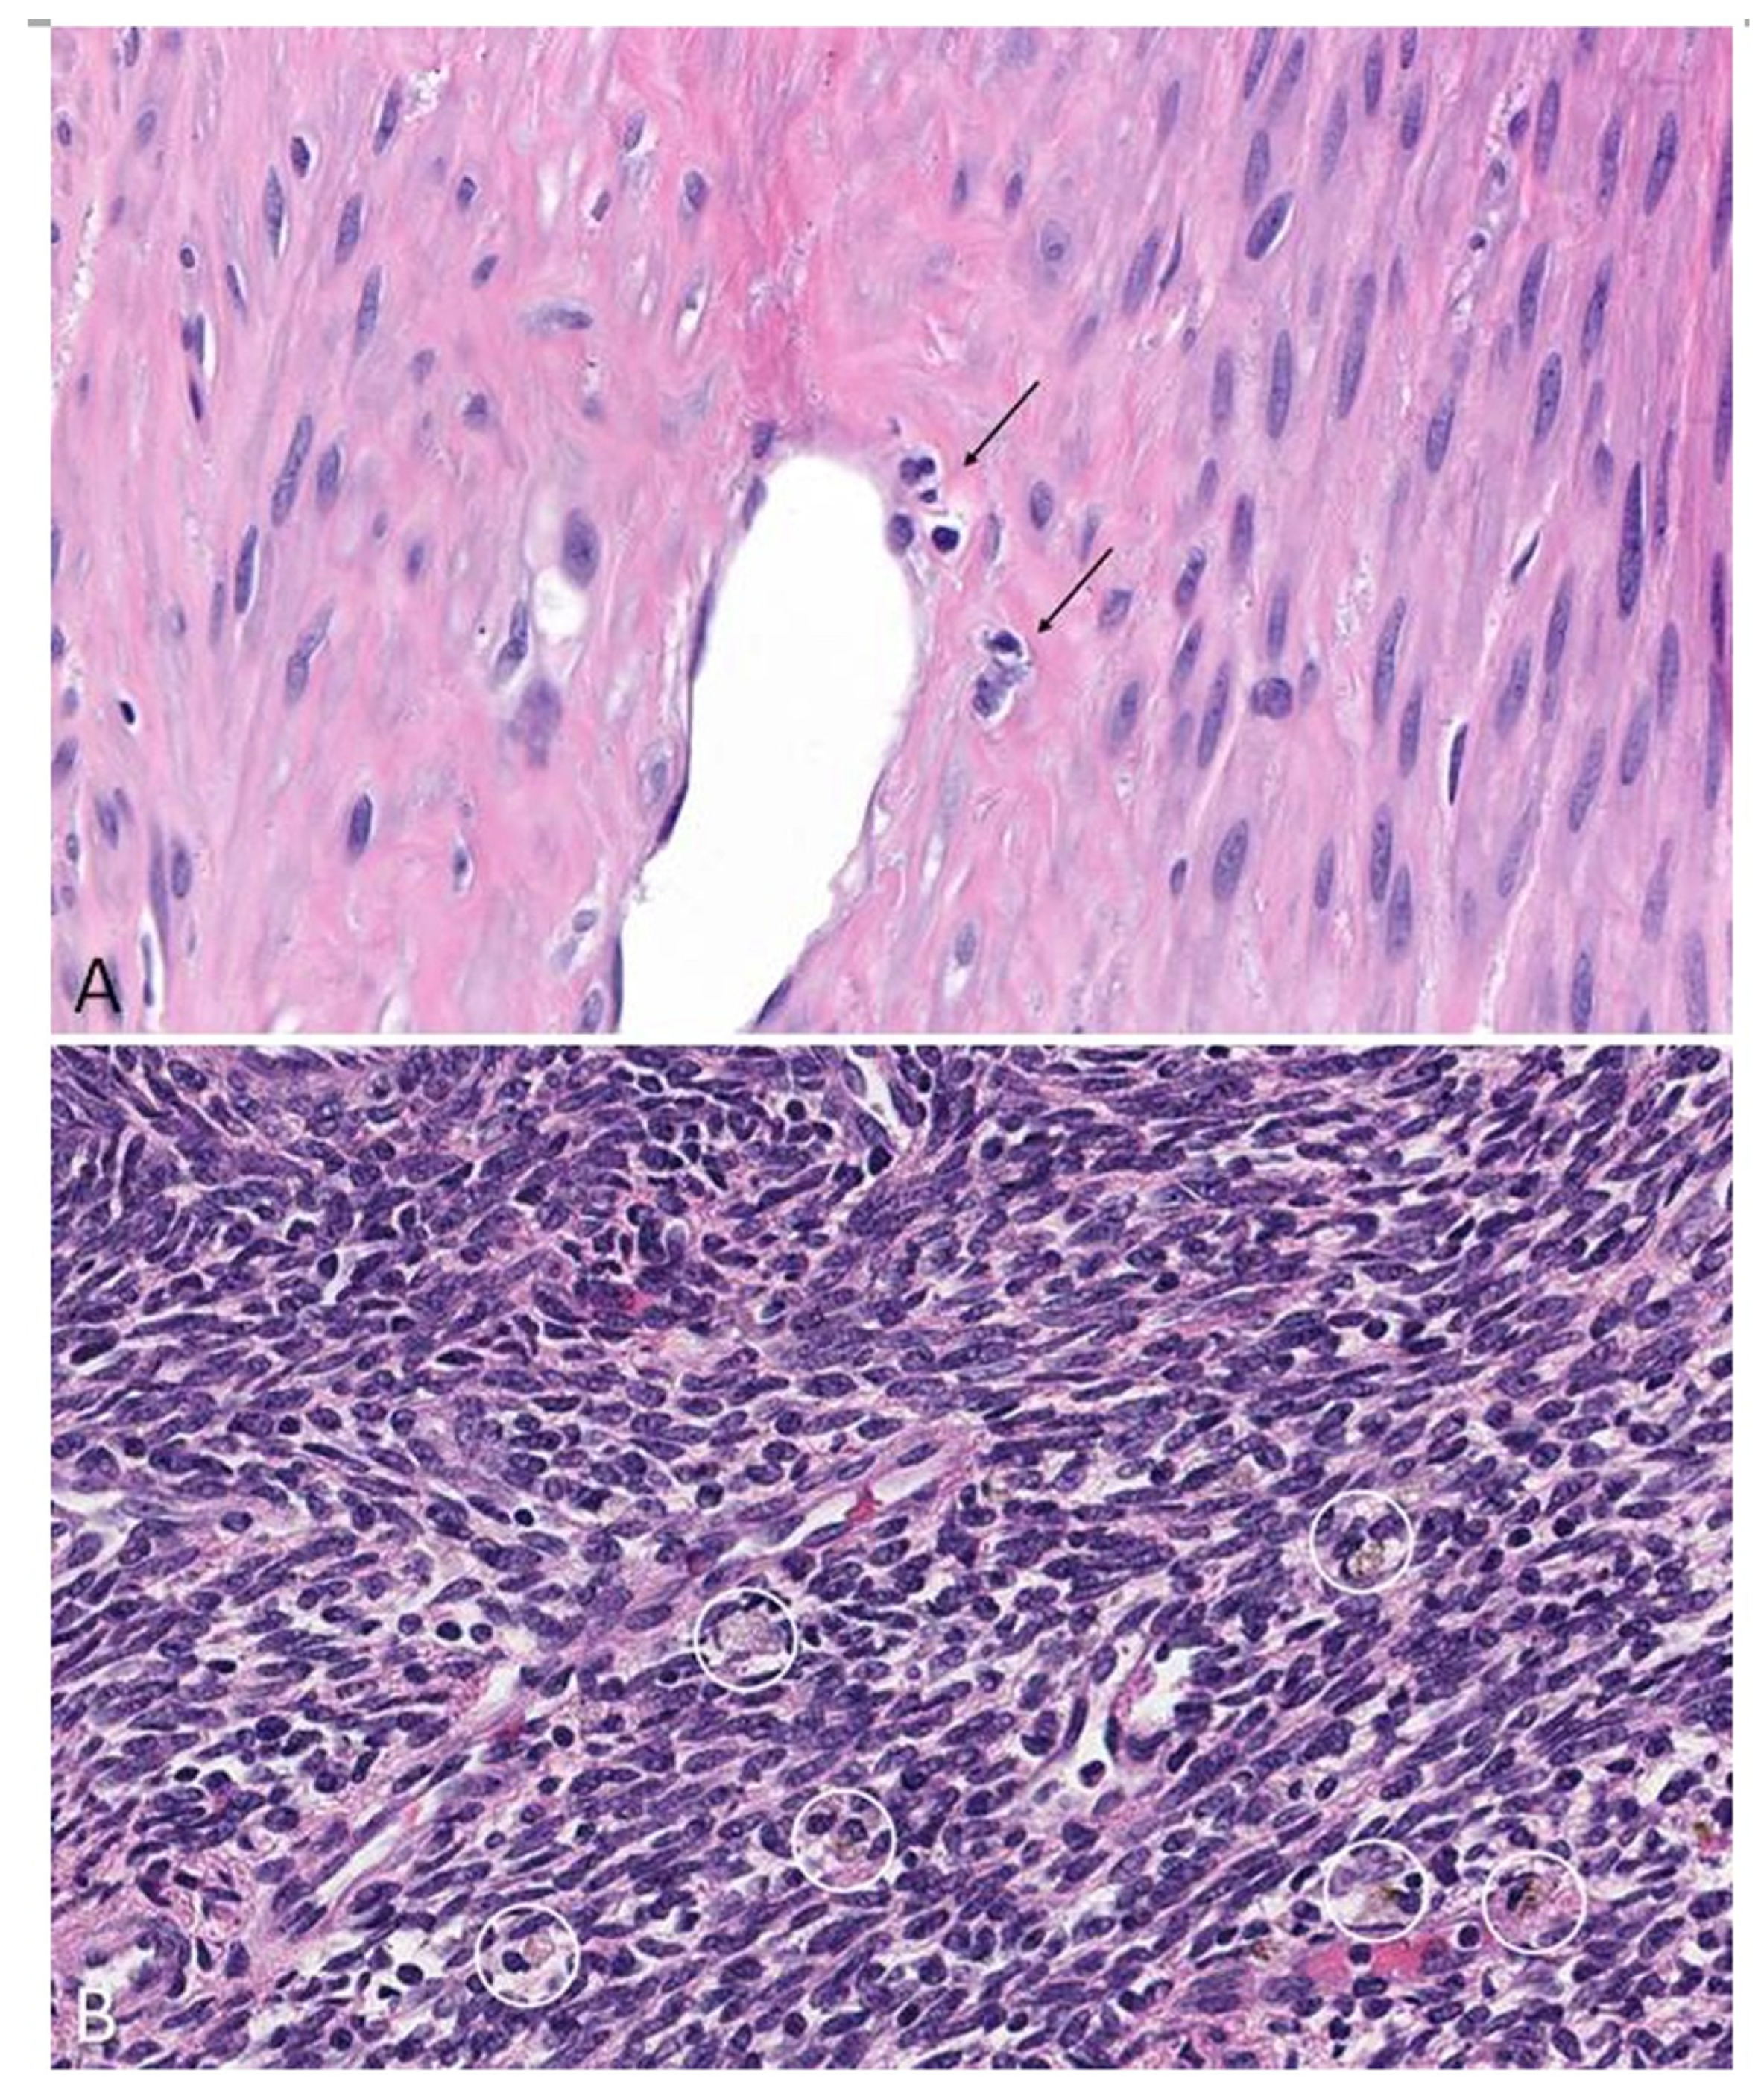

- Protic, O.; Toti, P.; Islam, S.; Occhini, R.; Giannubilo, S.R.; Catherino, W.H.; Cinti, S.; Petraglia, F.; Ciavattini, A.; Castellucci, M.; et al. Possible involvement of inflammatory/reparative processes in the development of uterine fibroids. Cell Tissue Res. 2016, 364, 415–427. [Google Scholar] [CrossRef]